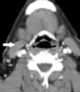

Sternocleidomastoid muscle hypertrophy

Spasmodic torticollis is an extremely painful chronic neurological movement disorder causing the neck to involuntarily turn to the left, right, upwards, and/or downwards. The condition is also referred to as "cervical dystonia". [Source: Wikipedia ]